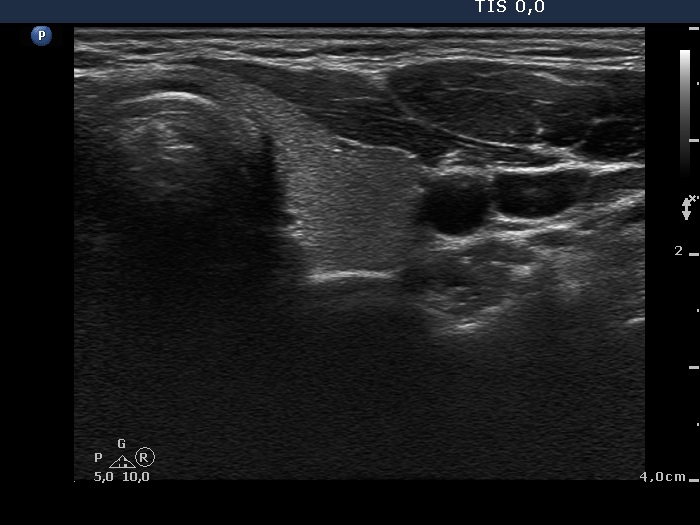

Third examination 24 months after initial investigation (3rd row of images)

Clinical data: The thyrostatic therapy was stopped 13 months ago. The patient had no complaints.

Palpation: unchanged.

Results of blood tests: euthyroidism (TSH 0.52 mIU/L, FT4 14.6 pM/L).

Ultrasonography: The size of the thyroid decreased further. The echo structure and the vascularization became normal.

Suggestion: to check the thyroid function every year, in the event of complaints or pregnancy at once.

Comment. This case demonstrates typical course of non-relapsing Graves disease. The change in hormone levels and in the ultrasound pattern are parallel.